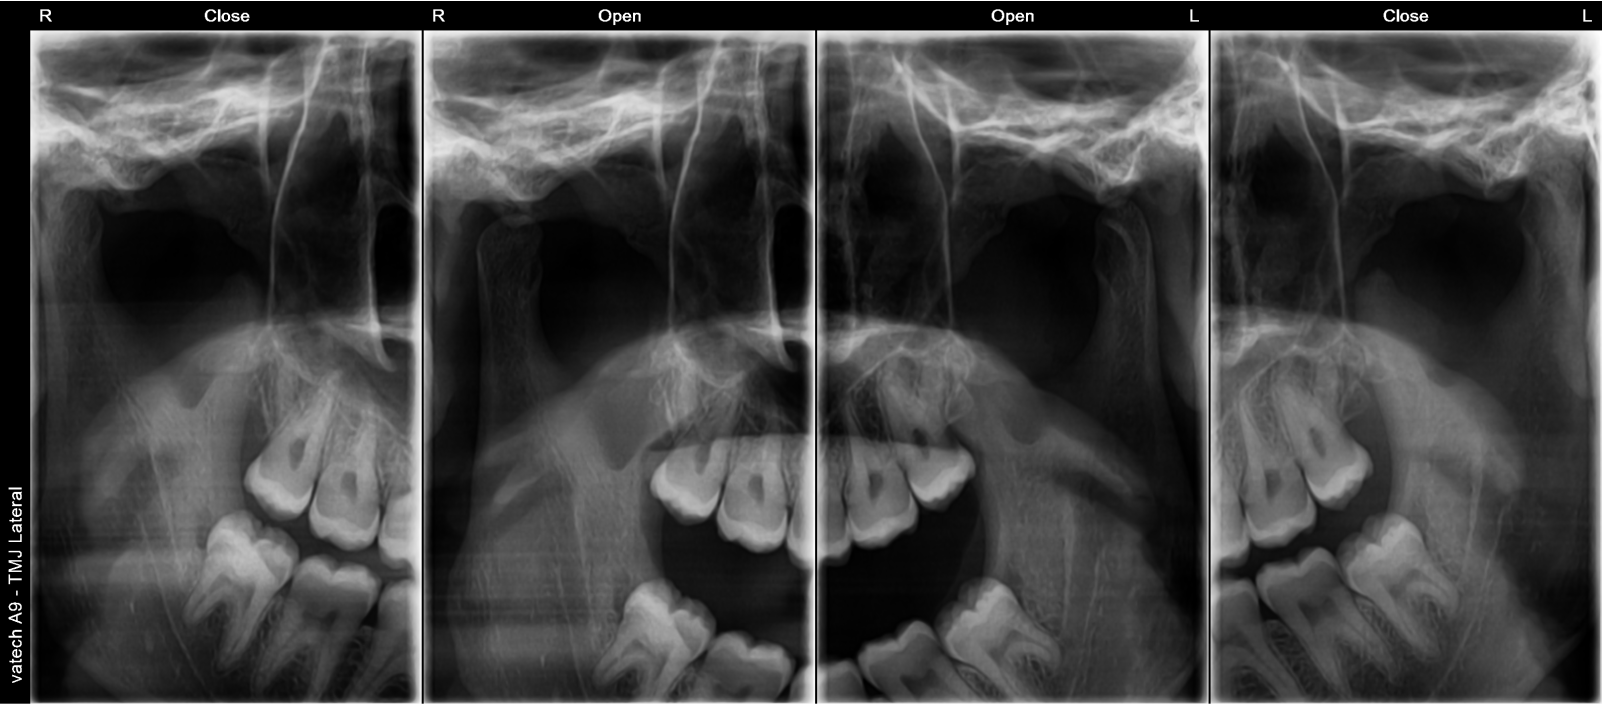

The Vatech A9 provides the most precise & high-quality panoramic images by combining image processing & accumulated experience in dental imaging from vatech. This will increase your diagnostic accuracy for improved treatment planning & patient satisfaction.